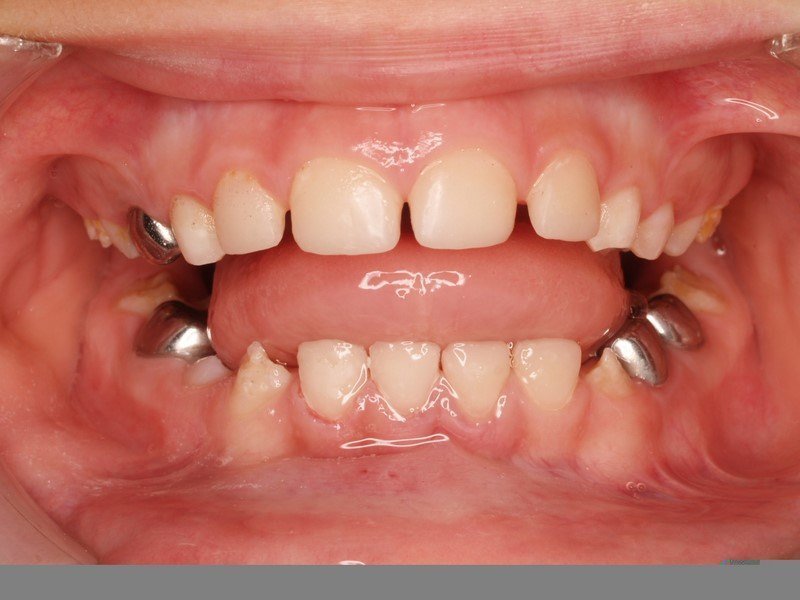

Niño de 8 años con retraso en la erupción de los dos incisivos centrales superiores y falta severa de espacio. Se trató con aparatología ortodoncica fija durante 10 meses.